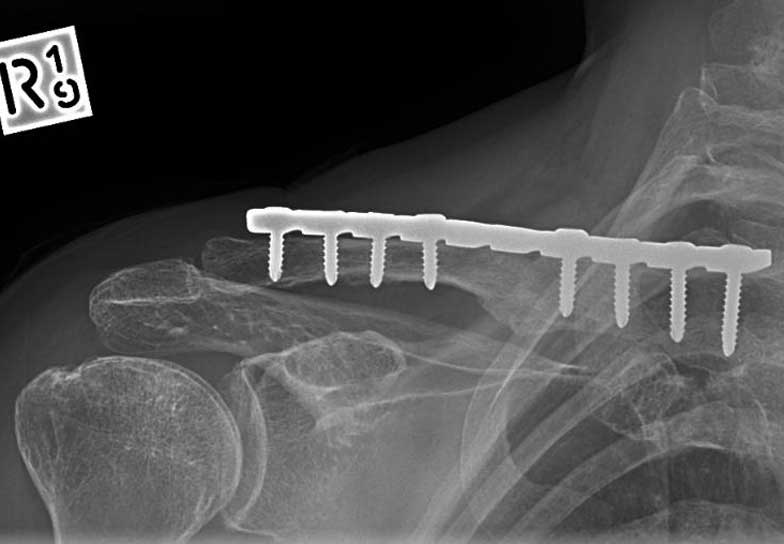

This is a 45 year old lady who fell from a horse fracturing her clavicle in at least 3 pieces.

The image on the left shows the fracture through the midpart of the clavicle and that it is in 3 pieces or more and displaced.

The image on the right shows the fracture fixed with plate and screws and 2 screws going in different directions to the plate to hold the separate fragments of bone in place.

Malunion fracture before surgery

Malunion fracture after surgery

Move the slider to compare before surgery and after surgery